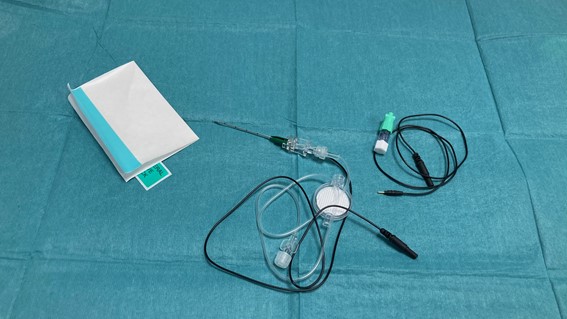

- Agujas: LocoplexÒ o EchoplexÒ de 35-50 mm. Aunque el plexo esté superficial generalmente se utiliza la aguja de mayor longitud para efectuar una única puerta de entrada en la piel.

- Fármacos utilizados. Habitualmente se usan de 20-30 ml de anestésico local. Para procedimientos de corta duración y con escaso dolor postoperatorio podemos utilizar Mepivacaína 1.5% o Lidocaína %. Para procedimientos más largos podemos utilizar Levobupivacaína o Ropivacaína 0.5%. Para uso como analgesia a través de catéteres (SilverstimÒ o MultiplexÒ) (Fig. 2) podemos utilizar anestésico local a más baja concentración (Ropivacaína 0.2% o Levobupivacaína 0.125 %), a unas dosis de 3-4 ml por hora y bolus de 2-3 ml con un tiempo de cierre de 30 minutos.